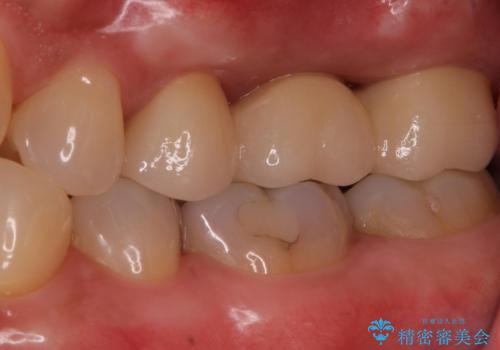

ブリッジでの修復は、抜歯後に歯がなくて噛みにくい期間が一切ありません。

歯茎の状態も良く、適合の良いブリッジを装着することができました。